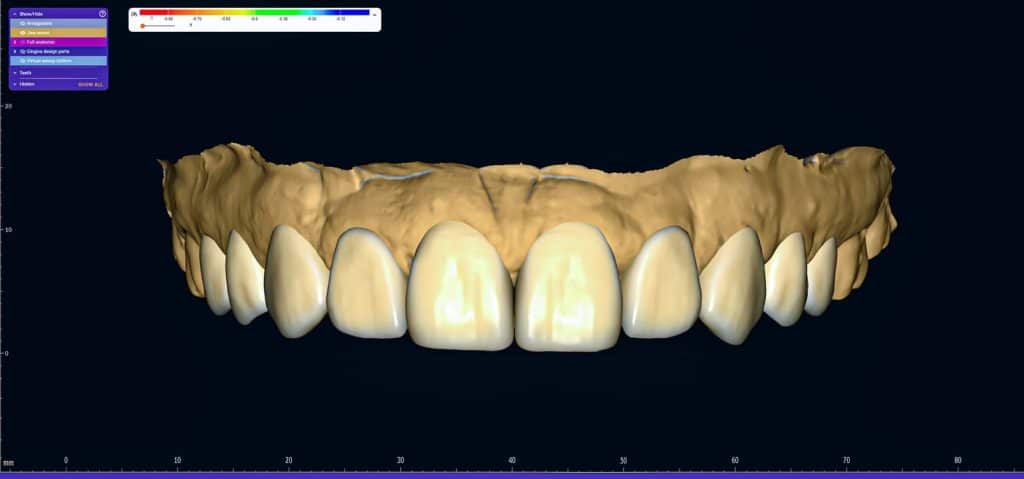

The case presented in this case report is for a 27-years-old female patient with a chief complaint of aesthetic correction for her smile. The patient was unhappy with her smile. After clinical examination, there were previous old composite veneering done poorly and incorrectly to close the multiple interdental spacing. After discussing the various treatment options (i.e., orthodontic treatment, direct, or indirect veneers), indirect ceramic veneering was selected. The step-by-step treatment protocol is presented in the images below.

Special thanks to my friend, Dr. Ali Al-Qrimli the CEO of Digital IDEA dental lab for fabrication of the ceramic veneers and the digital designing, with many thanks for the dental ceramist, Dt. Ali Kadum who did the ceramic build-up for this case.